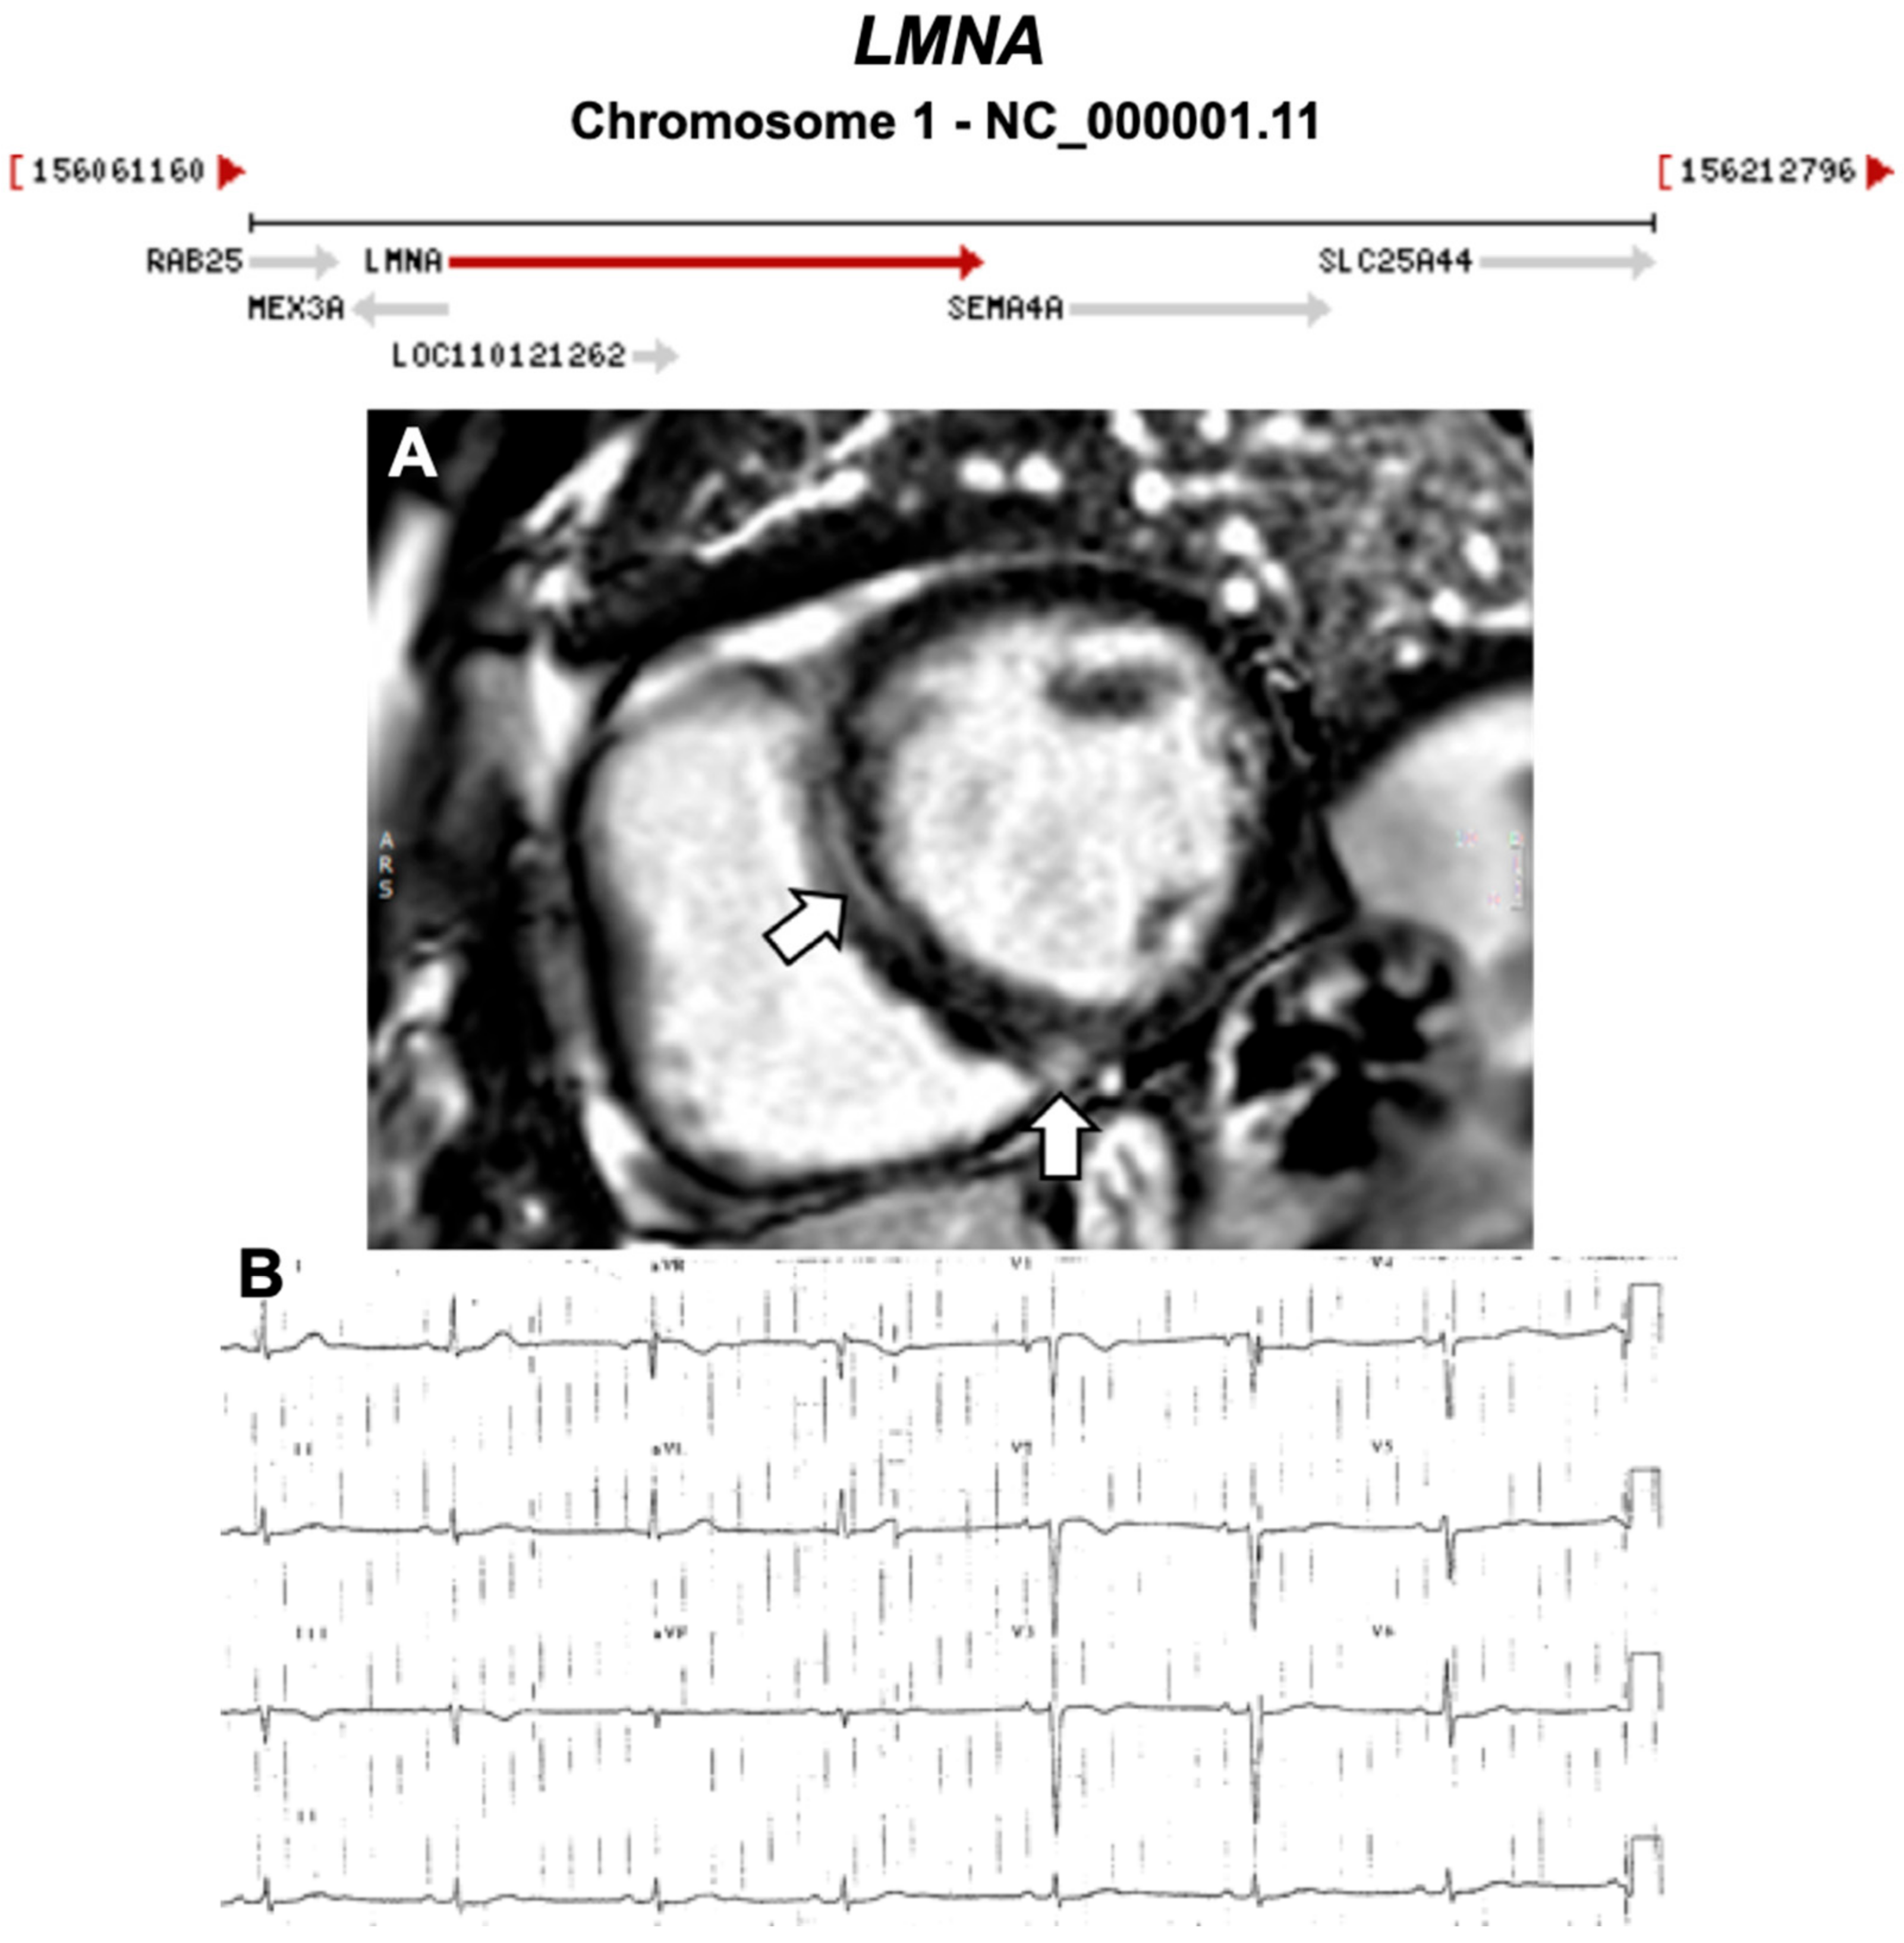

Figure 10.

Exemplar MRI and ECG finding found in ACM patients with LMNA mutations. (A) CMR of a patient with LMNA mutation showing a mid-wall (LGE) scar in the septum and inferior RV; (B) 12-lead ECG of a different patient with a p.Gly382Val LMNA mutation, which shows sinus bradycardia, poor R-wave progression, T-wave inversion in V1–V3 leads. (A) reproduced with permission from Augusto et al. (2019) [39]; and (B) reproduced with permission from Quarta et al. (2012) [41].